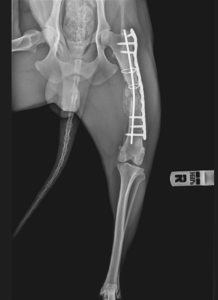

Licurici wurde in Rumänien mit einem Beinbruch auf der Straße gefunden. Wir sind sicher, dass er mal einen Besitzer gehabt haben muss (Licurici ist einfach viel zu menschenbezogen und kennt auch Halsband und Leine), doch dieser scheute vermutlich die Tierarztkosten und meldete sich nicht. Licurici möchte im Tierheim nicht alleine bleiben. Immer wenn er Menschenstimmen oder die anderen Hunde bellen hört möchte er auch dorthin und springt an der Türe hoch, um durch das Fenster schauen zu können. Dieses Springen ist aber überhaupt nicht gut für den Heilungsprozess den Beinbruchs und Dana weiß nicht mehr wie sie Licurici ruhig halten können. Er ist deswegen ja eigentlich so schon alleine in einem Zwinger untergebracht. Wenn er eine zweite Operation benötigen würde und so aktiv, jung und verspielt ist wie bisher, wird auch diese Operation vermutlich zum gleichen Ergebnis führen, sagt der behandelnde Tierarzt vor Ort. Daher wollen wir nun den Versuch starten ob sich vielleicht eine Pflegestelle in Deutschland findet, die Licurici bei sich aufnehmen kann, wo er ruhig gehalten werden kann und wo er nicht mehr alleine sein muss.